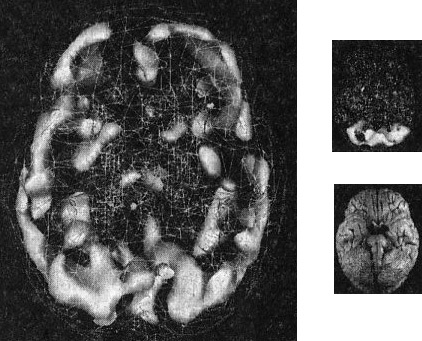

17-летняя Хитер очень много пила и не ладила с семьей. Я сделал томографию мозга ей и ее брату для телепередачи «Правда о выпивке», которая позже получила премию «Эмми».

На сканах вы видите области очень высокой активности (рис. 2.9). Неудивительно, что девушка начала пить — она пыталась успокоить свой мозг.

Гиперактивный мозг Хитер

Рис. 2.9 Вид функциональной активности снизу

Значительно снижена общая активность

45-летний Джимми обратился ко мне с посттравматическим стрессовым расстройством, вызванным пожаром. Томограмма показала множественные области повышенной активности, о которых можно было догадаться, судя по его тревожности, депрессии и страхам. Эмоциональные центры его мозга работали чересчур напряженно, и моей задачей было их успокоить (рис. 2.10).

Гиперактивный мозг Джимми

Рис. 2.10 Вид функциональной активности снизу

Повышенная активность в глубоких областях мозга